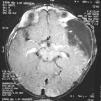

At three months of age, after an epileptic seizure, a 6 by 5 cm arachnoid cyst was discovered in the patient’s left middle cranial fossa (Figure 3). A cyst-peritoneal shunt was performed, and treatment was initiated with carbamazepine. Histopathology of the facial lesion confirmed Jadassohn’s sebaceous nevus (Figure 4). The patient currently presents a mild cognitive deficit and loss of visual acuity on the left. His twin sister is healthy.